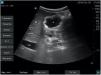

El riesgo elevado de aspiración pulmonar se asocia a la presencia de contenido sólido y de contenido líquido en un grado 22,3.

Presentamos 3 imágenes ecográficas realizadas con equipo Fujifilm® SonoSite SII y sonda cónvex C60xi de 2-5MHz: antro plano con paredes anterior y posterior unidas (vacío) en DLD, correspondiente con un grado 0 (riesgo bajo) (fig. 1); antro distendido con contenido anecoico (líquido) en DS, correspondiente con un grado 2 (riesgo elevado) (fig. 2) y antro distendido con contenido hiperecoico (sólido) en DS (riesgo elevado) (fig. 3).